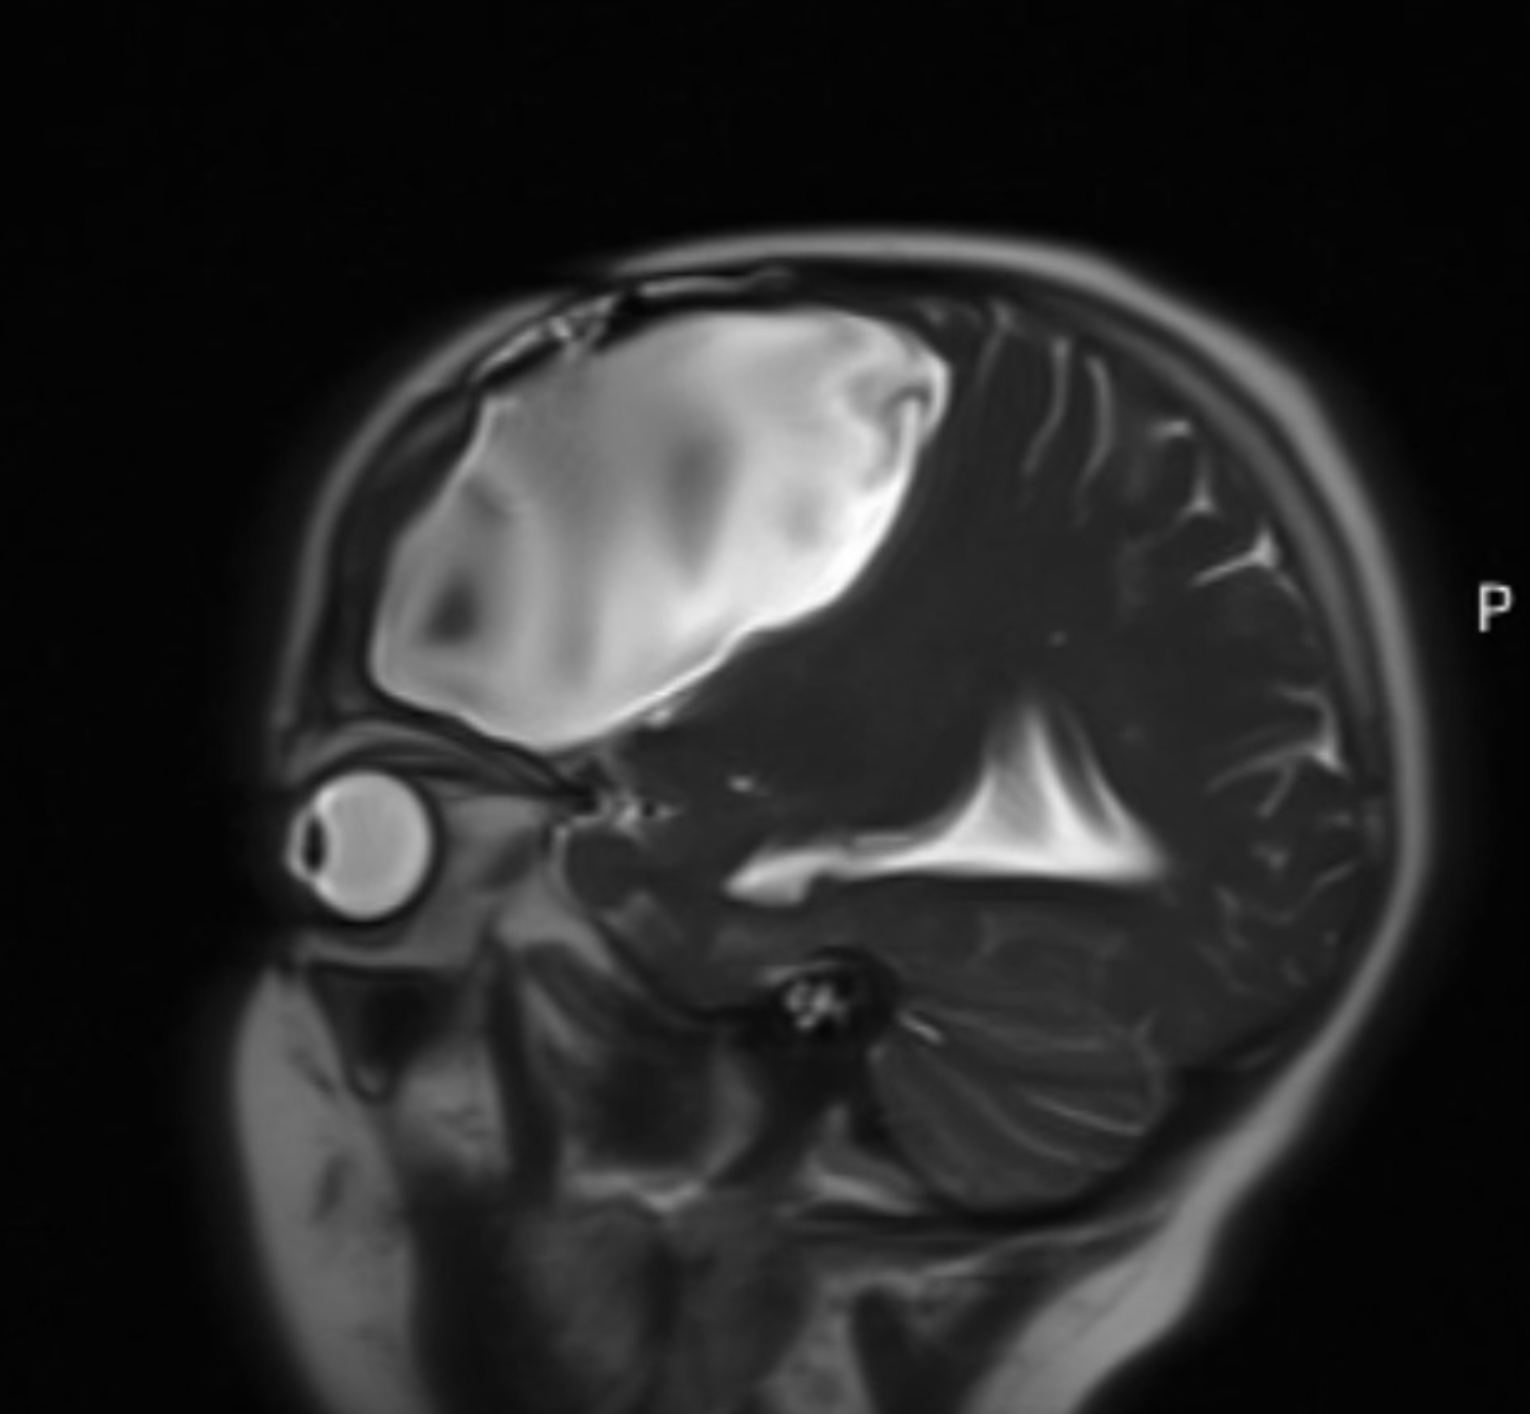

For those who don’t know me, my name is Alice Chawner. I’m 25 years old and I have a grade 4 Astrocytoma.

My diagnosis came unexpectedly during my first year at university, after a fall led to the discovery of what was then a grade 2 tumour.

But in June, just as I was due to start the trial, I was told the tumour had progressed to grade 3 or 4 and required immediate, urgent surgery.

I had surgery in July to remove as much of the tumour as possible ahead of radiotherapy. Although the procedure was successful, I became seriously unwell and spent six weeks in hospital. During that time, what was removed had already regrown, and was inevitably confirmed as grade 4.

I also tried two cycles of chemotherapy (Temozolomide), which left me bedbound for a week each month. In early February, a scan revealed a new aggressive tumour in a different part of my brain. The chemotherapy had not worked.